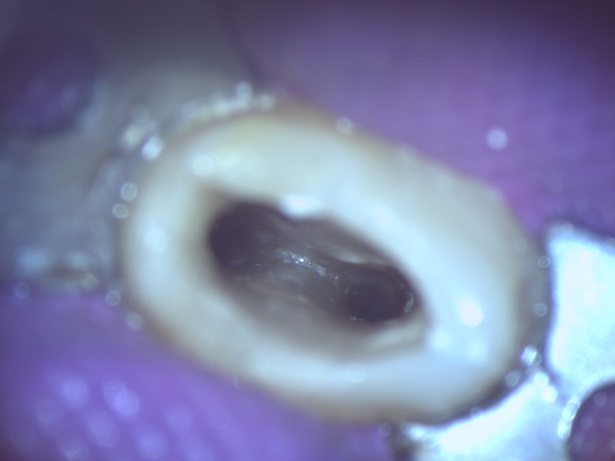

マイクロで中を綺麗にした根管 写真 根管3、4 |